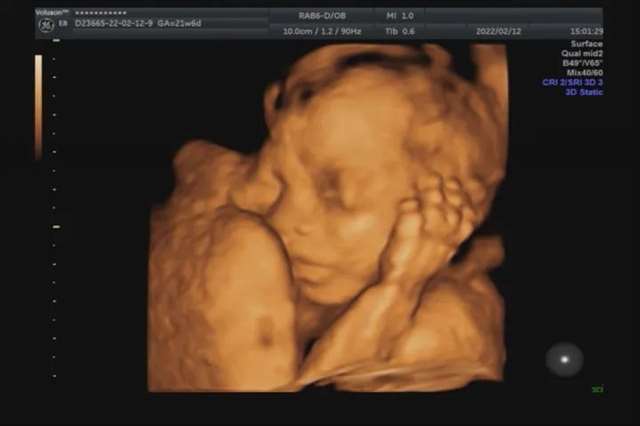

说起超声影像(四维彩超),很多孕妈妈都很期待与宝宝的第一次会面,渴望看到自家宝贝的“盛世美颜”。可是屏幕里这个塌塌鼻、大嘴巴、坑坑洼洼的“小泥人”简直让孕妈们的玻璃心碎成了渣~

这个答案其实是因人而异的,总的来说,宝宝出生后的样子与超声影像(四维彩超)中的图像不完全一样,应该说更好看一些。

像四维照片中有些宝宝的鼻子是扁的,这有可能是因为宝宝贴的妈妈肚皮太近了,脑补一下你把脸紧贴到镜子上是什么模样吧,又或者是当时脸部处的羊水比较少,也跟你拍照离镜头太近是一个道理哦。同时,超声影像(四维彩超)呈现的图像也跟当时的光线、宝宝的姿势有关。所以,孕妈妈不要太纠结超声影像(四维彩超)中宝宝的颜值,更多关注宝宝的健康才对呦〜

超声影像(四维彩超)的立体图像能更清楚地看到宝宝的五官,甚至还会有吃小手、打哈欠等淘气的模样,满足了孕妈妈想提前知道宝宝样子的好奇心,但是很多孕妈妈并不清楚,超声影像(四维彩超)和B超究竟有什么区别。

超声影像(四维彩超)需建立在二维超声切面基础上,采用四维成像技术,检查结果更为直观,立体,针对胎儿的生长发育做筛查,如发现唇裂、脊柱裂,大脑、肾、心脏、骨骼发育不良等情况,为早期诊断胎儿先天性体表缺陷和先天性心脏疾病提供准确的科学依据。